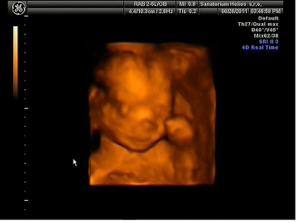

13.10.2011 Dle dnesniho 4D ma Emis 922g, kolik cm jsme se nedozvedeli, pry se to ted urcuje spatne.. Jinak to vypada, ze nosanek bude mit po tatinkovi a pusinku po mamince;) Moc se ji hybat nechtelo, spinkala, obcas se pohla, dala rucicky pred oblicej, nozku pres nozku a taky se usmala🙂)

1.11.11 ko 29+1, Emisatko ma 1200g, dle biometrie je o cca tyden mensi (28+2), ale nozky ma delsi:D pry je porad v norme, plodovky ma dost, v cekarne radila, kdezto na utz mela pulnoc🙂 odebrana krev, CS 0, dalsi ko 22.11. a k 21.11. nastup na materskou🙂